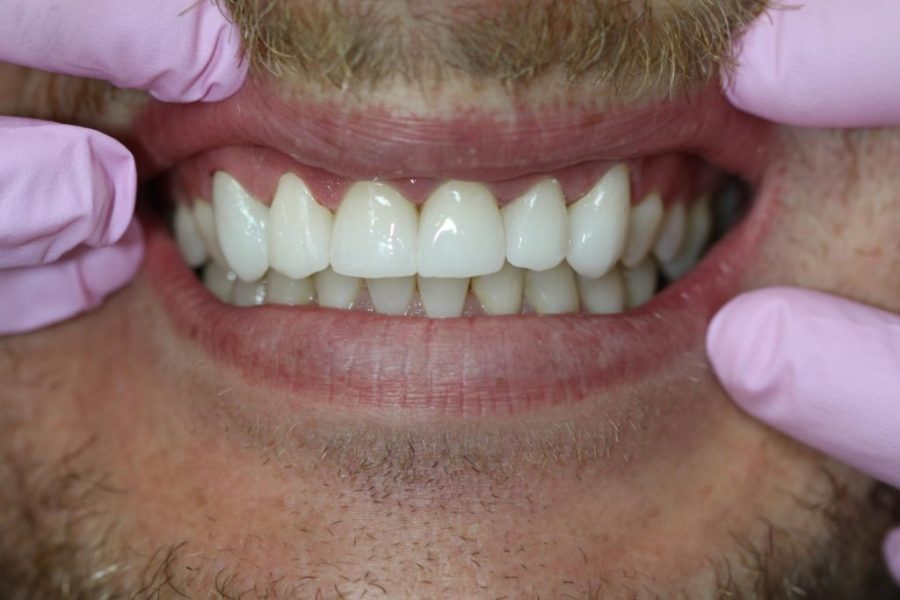

Frank’s Story: Repairing Damage with Dental Crowns

Frank, a kickboxer and teeth grinder, came to us for help. We placed six crowns on his front teeth, giving him a strong and stunning smile. Frank now spends more time dodging punches than worrying about his teeth!